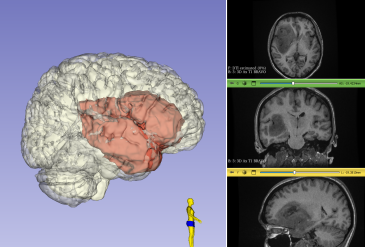

Удаление злокачественной астроцитомы Grade IV WHO в правой теменно-затылочной области Добавлено 27.06.202418.01.2026 Читать далее

Удаление злокачественной астроцитомы Grade IV WHO в правой темнее-затылочной области Добавлено 10.08.201518.07.2016 Читать далее